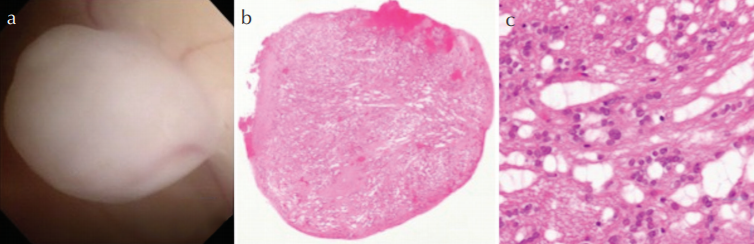

a内镜下显示一个清晰、坚实的白色肿块突出到侧脑室。b-c. 缺乏异型性的椭圆形细胞簇嵌在纤维背景中,微晶结构在中部突出。